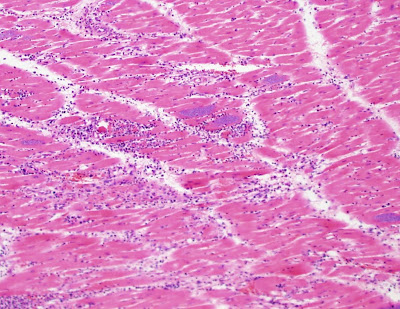

A 50 year old male from South America died suddenly and an autopsy was performed. show are hematoxylin and eosin stained tissue sections of myocardium (heart muscle). Diagnosis? (CLICK ON IMAGES TO ENLARGE)

Yep I'll agree T cruzi amasatagotes; the aetiological agent of Chagas Disease.

T. cruzi amastigotes.